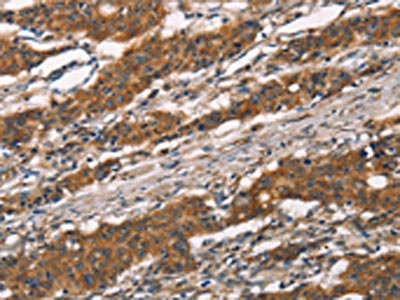

The image on the left is immunohistochemistry of paraffin-embedded Human gastic cancer tissue using CSB-PA174054(MMP2 Antibody) at dilution 1/30, on the right is treated with synthetic peptide. (Original magnification: ×200)

The image on the left is immunohistochemistry of paraffin-embedded Human thyroid cancer tissue using CSB-PA174054(MMP2 Antibody) at dilution 1/30, on the right is treated with synthetic peptide. (Original magnification: ×200)